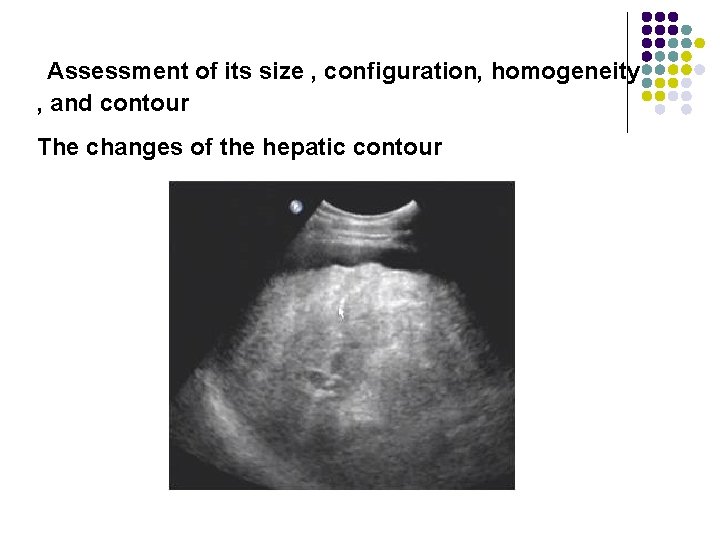

Pathology of the Live l Evaluation of the liver parenchyma includes the assessment of its size , configuration, homogeneity , and contour.

Assessment of its size , configuration, homogeneity , and contour

Assessment of its size , configuration, homogeneity , and contour The changes of the hepatic contour